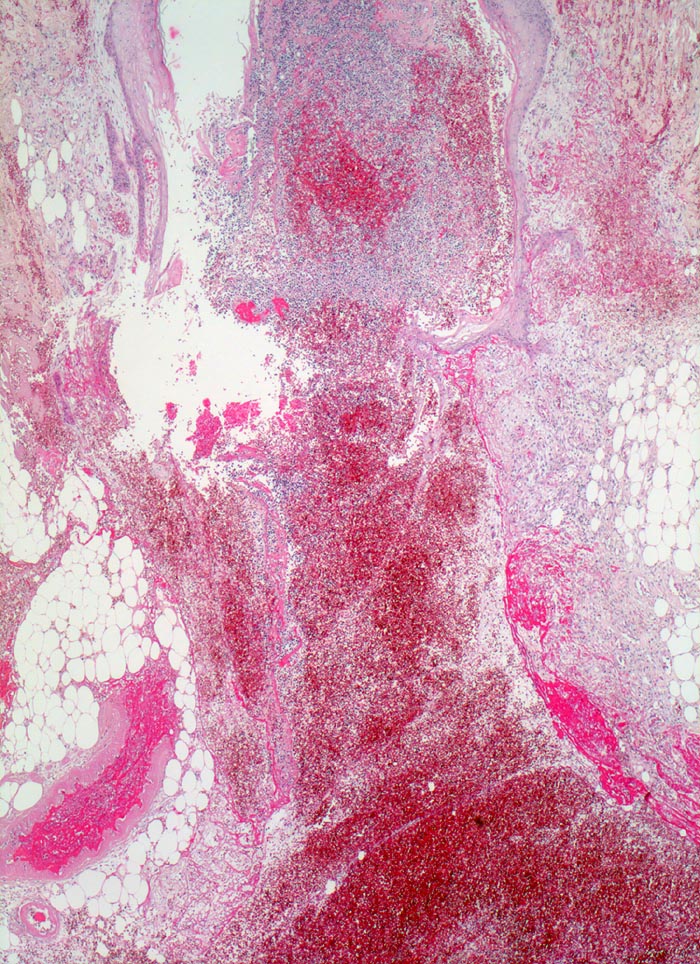

Morphologische Merkmale:

• Schlitzförmiger, bis in die Subkutis reichender Hautdefekt.

• Neugebildete Epidermis bedeckt im oberen intradermalen Anteil des Wundspaltes teilweise den Gewebsdefekt.

• Daran angrenzender Wundspalt im Bereich des subkutanen Fettgewebes mit Fibrinauflagerungen und ödematösem zellarmem Granulationsgewebe.

• An der Basis des Präparates Auseinanderklaffen des Wundspalts wegen grösserem Blutkoagel (verursacht Wundheilungsstörung).